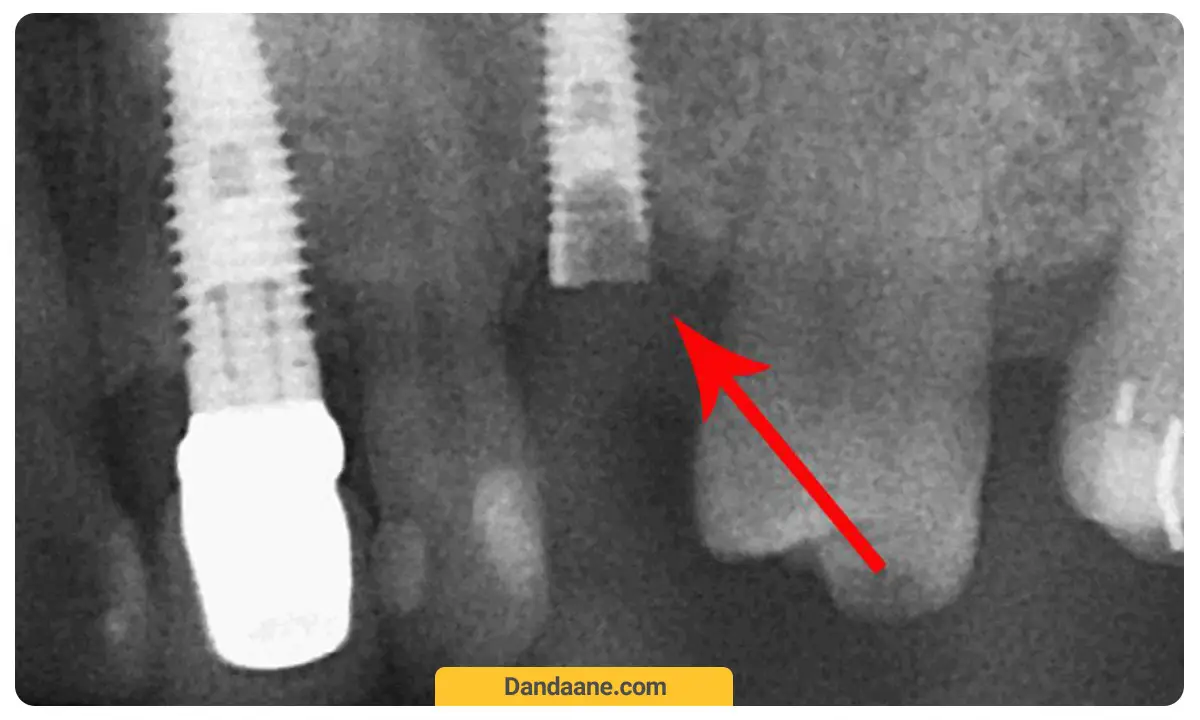

6. صدمه دیدن سینوس ماگزیلاری

سینوس ماگزیلاری یک ساختار حفره مانند در دو طرف صورت ما است که در بالای دندان های آسیاب فوقانی در فک بالا قرار دارد. اگر به دلیل پایین بودن قیمت ایمپلنت دندان گول متخصصانی را خورده باشید که کم تجربه باشند احتمال دارد حین وارد شدن ایمپلنت به استخوان، جداره سینوس آسیب ببیند. در این وضعیت عوارض جدی متوجه شما خواهد شد.